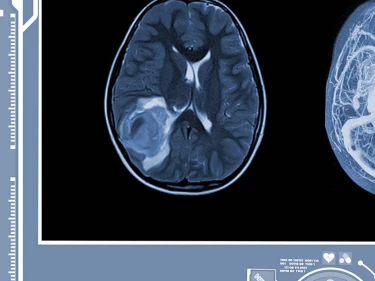

Motorcycle accidents can cause a range of brain injuries, each with its own set of risks and symptoms. A mild TBI, often referred to as a concussion, may result in temporary cognitive impairments such as confusion or memory loss. Severe TBI, on the other hand, can lead to permanent brain damage and long-term cognitive impairments that affect every aspect of daily life. Diffuse axonal injury is another serious type, occurring when the brain’s nerve cells are stretched or torn, leading to both cognitive and emotional symptoms. Additionally, common brain bleed symptoms and types such as subarachnoid hemorrhage, epidural hematoma, and subdural hematoma can develop when blood vessels rupture, causing blood to pool and put dangerous pressure on the brain. Left untreated, these injuries can have severe or even fatal consequences.

Intracranial bleeding can cause death. In the most severe cases, a brain bleed from a motorcycle accident can result in brain death, a condition where all brain function irreversibly ceases due to catastrophic brain damage. It may also permanently damage the brain or cause the victim to become comatose. In some cases, doctors can relieve the pressure on the brain by draining fluid from the skull. However, brain cells do not regenerate, so any sustained pressure damage will be permanent.